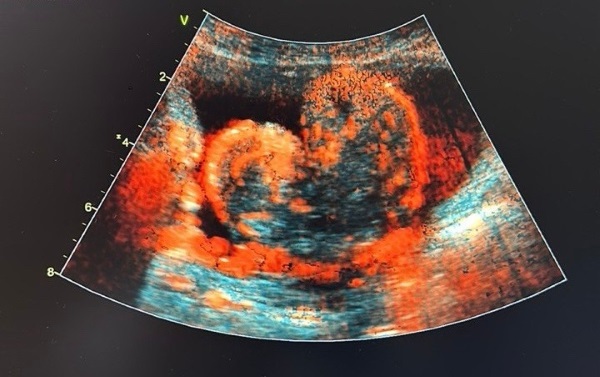

У жителя Бурятии появилась опухоль в виде сердца

Она «выросла» из простаты

Этой историей поделились в Бурятском онкологическом диспансере. В минувшую субботу, 14 февраля, узисты обнаружили у жителя республики опухоль в виде сердца.

Как выяснилось, она выросла из простаты. Снимок опубликовали на официальной странице медучреждения во «ВКонтакте».